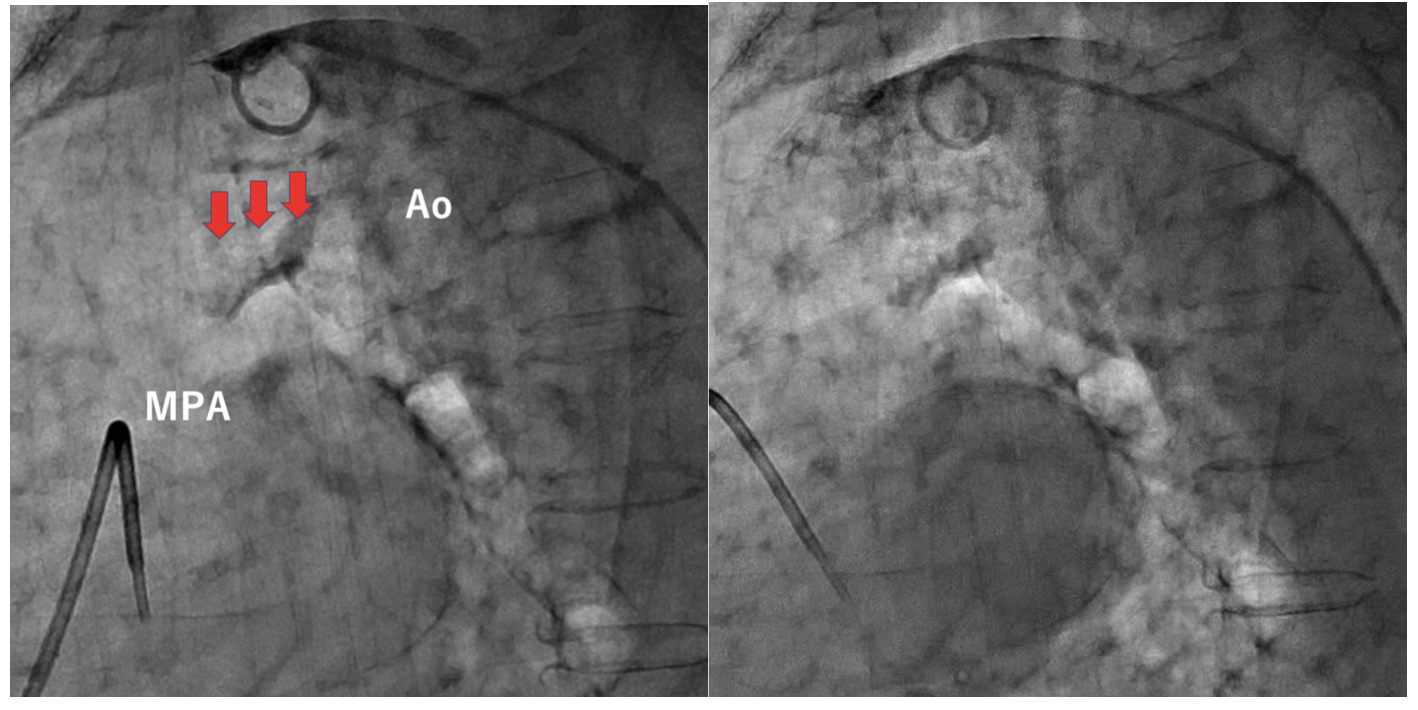

An 89-year-old woman was referred for closure of a patent ductus arteriosus (PDA). Contrast-computed tomography showed Krichenko type C PDA with severe calcification (Figure 1). Initial angiography revealed severe calcification of the PDA (Figure 2, Video 1), and the mid-ductus diameter was 6 mm and the ductus length was 14 mm.

We chose re-intervention for the residual shunt. Intravascular ultrasound revealed that an incomplete closed space outside the ADO II caused the residual shunt (Figure 3, Video 2). We concluded that the ADO II device was over-stretched and not well-positioned due to severe calcification of the PDA. An Amplatzer Vascular Plug II (AVP II) (Abbott) 14/10 was deployed in the space (Figure 4, Video 3), and the PDA flow disappeared completely.